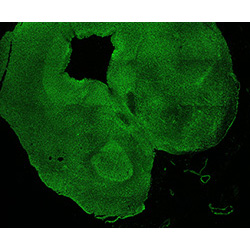

An anatomical analysis of the developing human midbrain from 6 post-conceptional weeks (PCW) to 22 PCW reveals increased tissue complexity, characterized by the emergence of dopaminergic nuclei, as highlighted by immunofluorescence analysis for tyrosine hydroxylase (TH).

MAP2

11PCW human midbrain